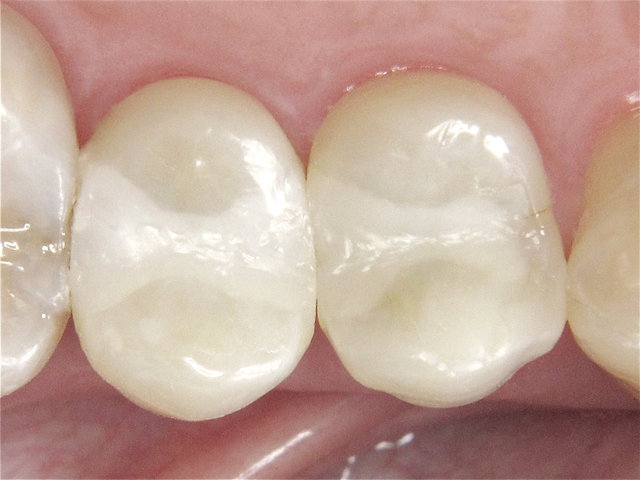

Alte Amalgam-Füllungen mit Sekundärkaries ...

Composit-Füllungen by CLINICDENT ✓